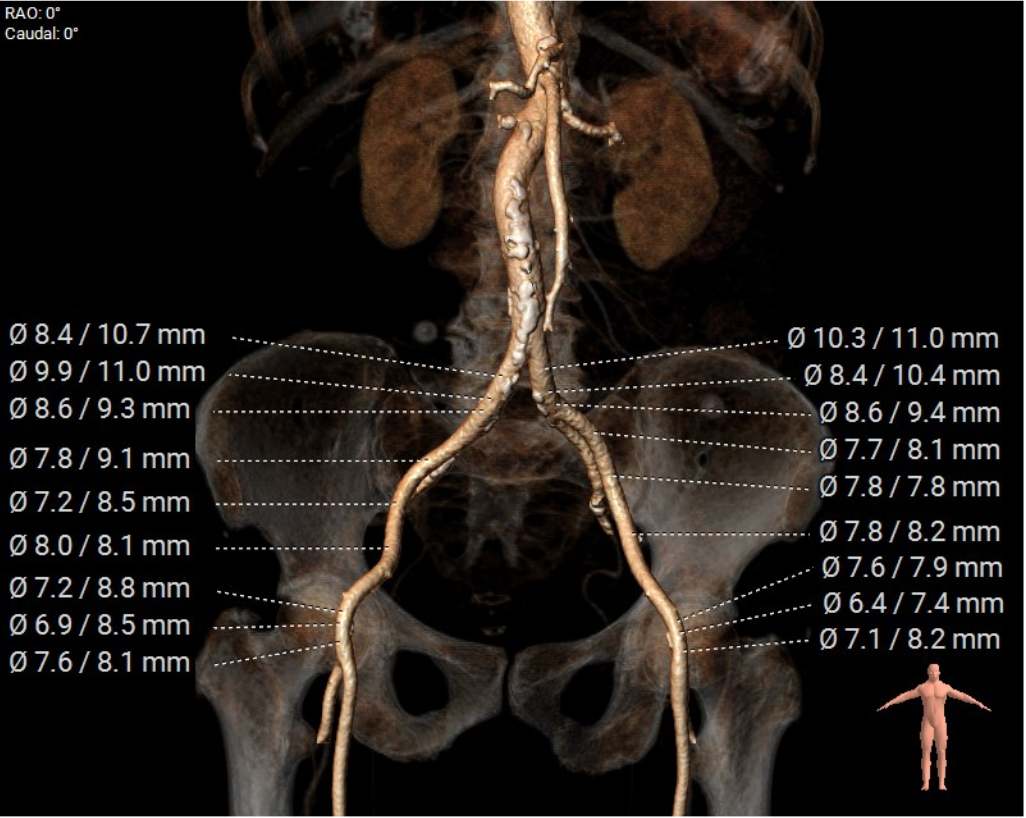

股动脉入路: